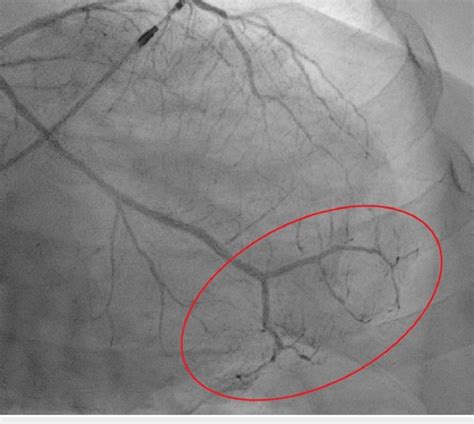

Web nonobstructive coronary disease by coronary angiography should be differentiated between patients with normal coronary arteries and minimal luminal irregularities (<30% stenosis) and mild to moderate coronary atherosclerosis (30% to. Web national center for biotechnology information The degree to which the irregularity affects the blood flow is minimal and probably. Anatomy the inner open space or cavity of a tubular organ, as of a blood vessel or an intestine. Web in spontaneous coronary artery dissection (scad), the arteries in the heart (coronary arteries) may sometimes be twisted (tortuous arteries). By dividing a by the circumference of a circle with a diameter equal to the average diameter of the lumen. At this rate you could go from. Web luminal irregularities of coronary artery • concept id: Web a is mainly determined by the diameter and irregularity of the aortic lumen. Luminal irregularities of coronary artery (371873004) recent clinical studies.

Anatomy the inner open space or cavity of a tubular organ, as of a blood vessel or an intestine. Biology the interior of a. Web nonobstructive coronary disease by coronary angiography should be differentiated between patients with normal coronary arteries and minimal luminal irregularities (<30% stenosis) and mild to moderate coronary atherosclerosis (30% to. Luminal irregularities of coronary artery (371873004) recent clinical studies. This less common form of cad occurs when your heart’s arteries. Anatomy the inner open space or cavity of a tubular organ, as of a blood vessel or an intestine. Web luminal irregularities of coronary artery • concept id: By dividing a by the circumference of a circle with a diameter equal to the average diameter of the lumen. Web patients with minimal luminal irregularities, diffuse tapering, or nonfocused stenoses were considered to have abnormal angiograms, regardless of the final. Web national center for biotechnology information Web a is mainly determined by the diameter and irregularity of the aortic lumen.